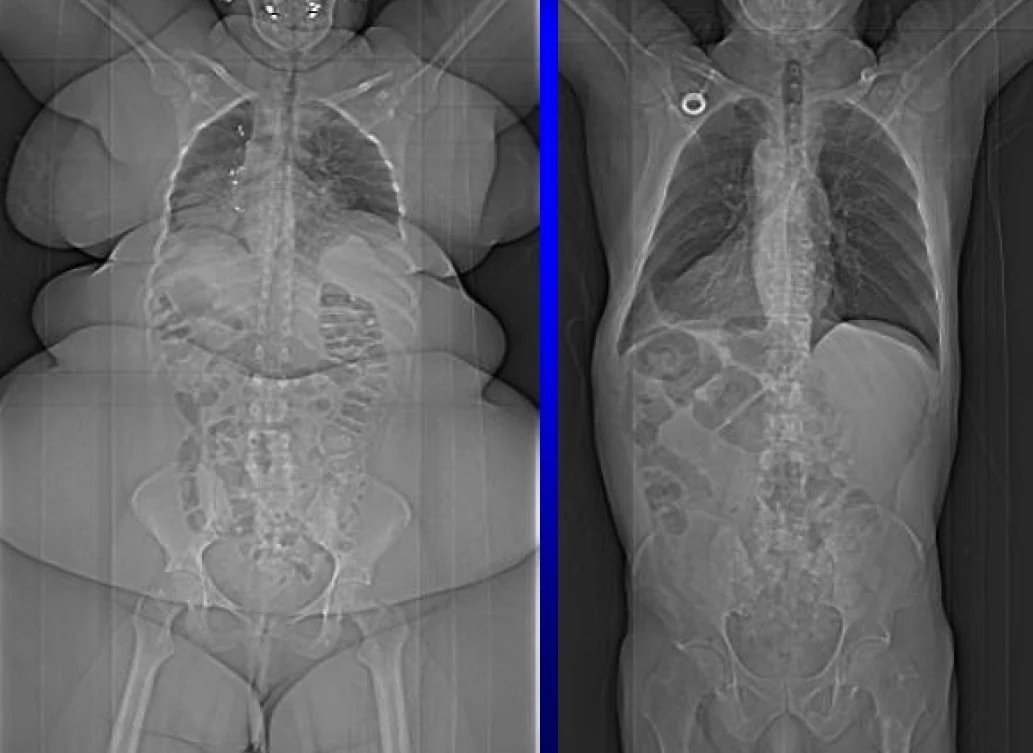

Too much fat gets stored in your liver and pancreas, creating a vicious cycle that wrecks your metabolism. Image